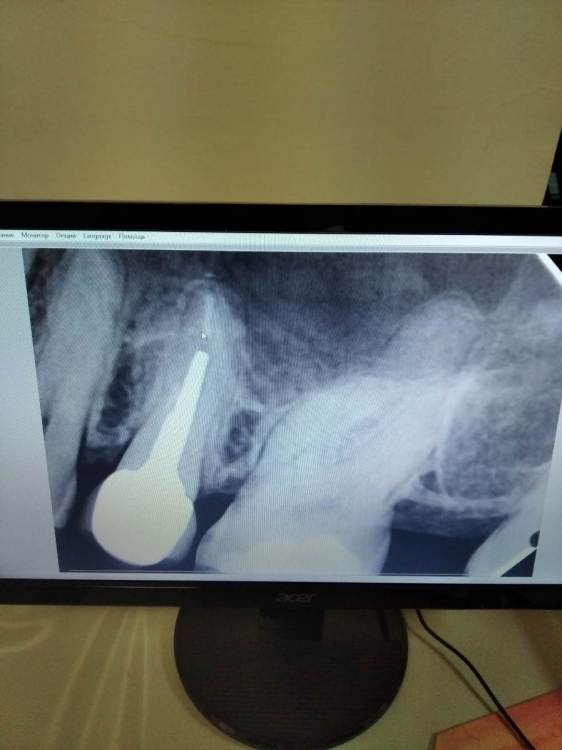

Елена8 Опубликовано 24 января, 2022 Поделиться Опубликовано 24 января, 2022 Добрый день) Скажите, пожалуйста, что это? Извиняюсь, я сфотографировала. По-другому там не получалось. У меня уже несколько недель болят зубы. Началось почему-то все после ОРВИ. Вначале было ощущение, что болит вся верхняя челюсть и отдает в лицо. Боли были ноющие, начинались под вечер. Сходила к одному стоматологу. Она сказала, что что-то с деснами в зубе мудрости и положила туда лекарство. А у меня как болело - так и продолжало болеть. Пошла к другому стоматологу. И вот она просто никак не может понять причину... Другим врачам при мне показывала снимки - никто ничего не знает, не понимает... КТ не могу скинуть. Своими словами скажу. Там кариес двух зубов, который при обычном осмотре не видно. Но как врач мне сказала - он далеко от нерва. В итоге она сказала, что у меня болезненные карманы. Их два. И вот она уже второй раз кладет лекарство в один из них. Один раз она это делала с анестезией, второй раз - без. Боль просто дикая... После лекарства картина поменялась. Теперь болит не все время. Но сильные боли тоже бывают. И как мне кажется - сейчас боли не ноющие, а дергающие. Вначале пила нимесил, но его долго нельзя. Теперь, когда болит, найз пью. Сегодня врач отправила меня к пародонтологу. Сказала - пусть он исключит со своей стороны. Если там ничего нет - она будет удалять нерв. Она меня просто замучила уже. Помогите, пожалуйста. На снимках видно что это? Ссылка на комментарий

Елена8 Опубликовано 26 января, 2022 Автор Поделиться Опубликовано 26 января, 2022 Сегодня снимки посмотрела пародонтолог. Сказала, что это и карман, и кариес 6-го зуба. А с ее стороны все нормально. Сейчас уже ничего не болит. Смотрите, у меня такой вот вопрос. Я запишусь кариес лечить. А с карманом нужно делать что-то? Его лечат как-то? Мне сказали только полоскать и пользоваться зубной нитью. А врач может что-то сделать? И будет ли он дальше болеть, если от лекарства он болеть перестал? Ссылка на комментарий